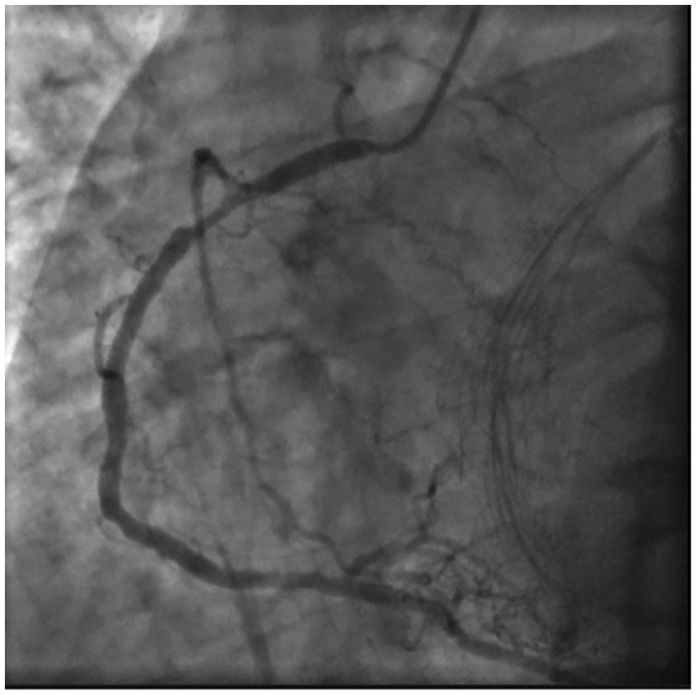

A 55-year-old male patient was referred to our transplantation clinic. The patient was on a 3/7 dialysis program. During his cardiac assessment, electrocardiogram (ECG) findings were non-significant, and his left ventricular ejection fraction (LVEF) was 58%. He was on colchicine treatment for mild pleural and pericardial effusion. Myocardial perfusion scintigraphy (MPS) revealed anterior and apical non-reversible and reversible perfusion defects. Three-vessel CAD was diagnosed by coronary angiography (CAG) (Figures 1, 2). An off-pump CABGx3 [the left internal mammary artery to the left anterior descending artery (LIMA-LAD), aort to right posterior descending artery (Ao-RPD), Ao to second optuse marginal branch of circumflex artery (Ao-CxOM2)] was performed without the use of blood products. The patient's pre-CABG laboratory values were as follows: hemoglobin (Hgb) 8.5 g/dl, hematocrit (Hct) 24.6%, platelets (PLT) 172,000/μl, and creatinine (Cr) 6.67 mg/dl. Post-CABG, the following values were measured: Hgb 7.61 g/dl, Hct 22.8%, PLT 146,000/μl, and Cr 9 mg/dl. On post-CABG day 5, the patient was transferred to nephrology while continuing oral cardiac treatment.

Figure 2

Coronary angiography view of RCA proximal 90% stenosis.